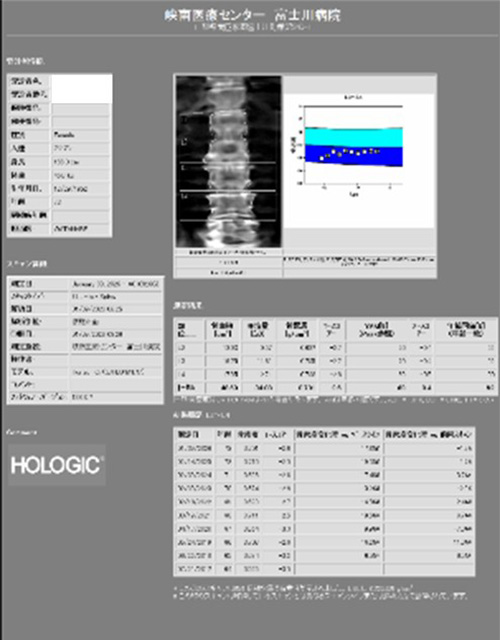

骨密度測定

骨を構成するカルシウムなどのミネラル成分の量をX線を用いて測定する検査です。主に骨粗しょう症の診断や投薬治療による骨量の変化に用います。当院では2つの異なるX線エネルギーを使用する測定法のDEXA法を用いて腰椎、大腿骨の骨密度を測定します。検査時間は10分から15分くらいになります。